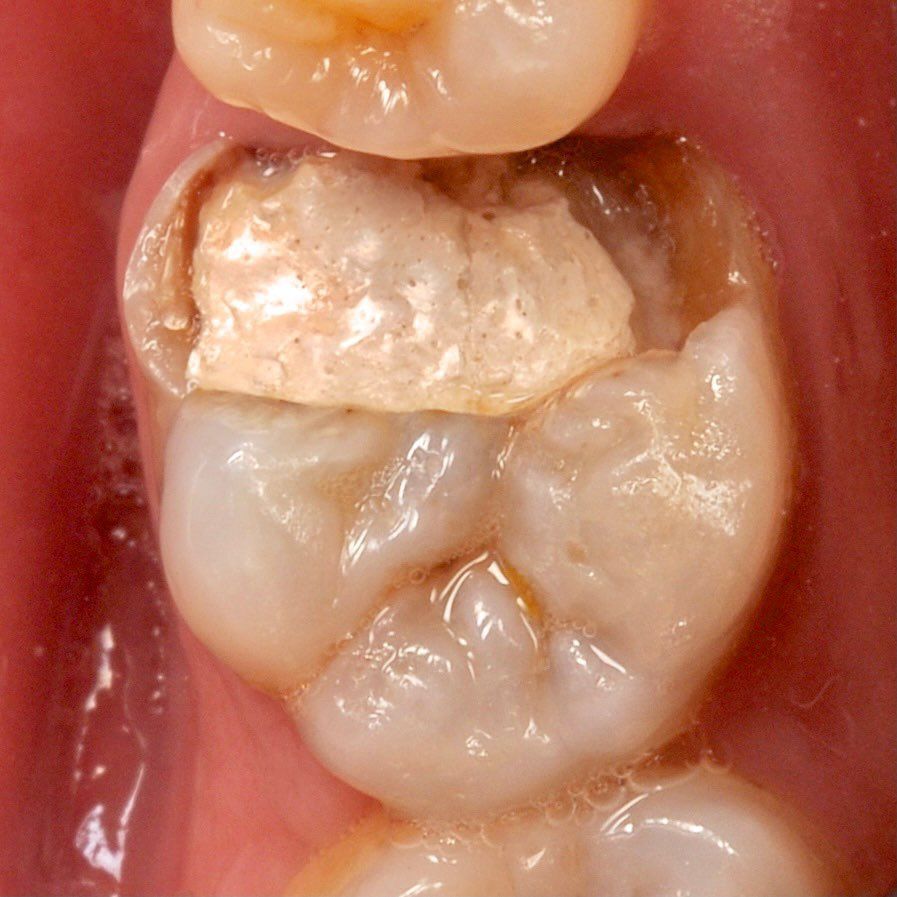

we install a crown on the cured tooth

We prosthetics a tooth, we protect it from the external environment

As a result, we make dentures after endodontic treatment and give confident guarantee with no worry.